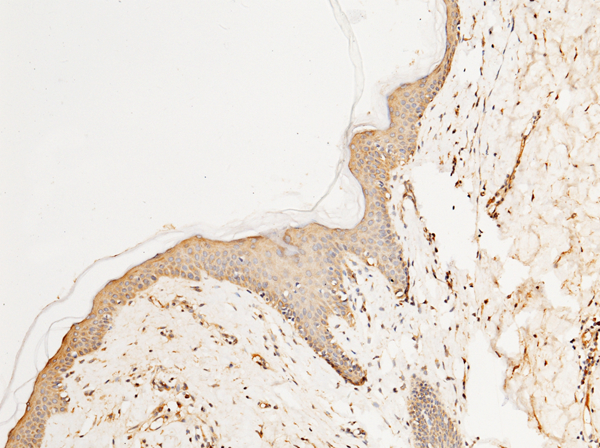

IHC (Immunohistochemistry)

(Immunochemical staining of human SPARC in human skin with rabbit polyclonal antibody (1:1000, formalin-fixed paraffin embedded sections).)